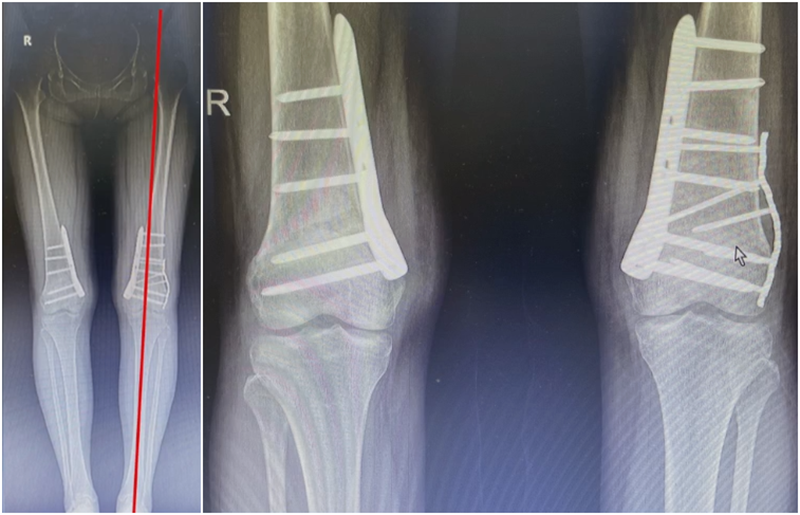

近端螺钉松开,调整力线,重新固定后,在外侧加小钢板抗旋。

术后10周复查,力线较好。